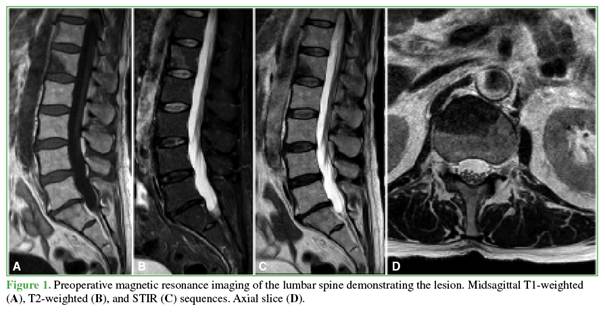

Postoperative images

Postoperative computed tomography confirmed correct pedicle screw placement and absence of intracanal cement leakage (Figure 2). No signs of spinal canal compression were observed.